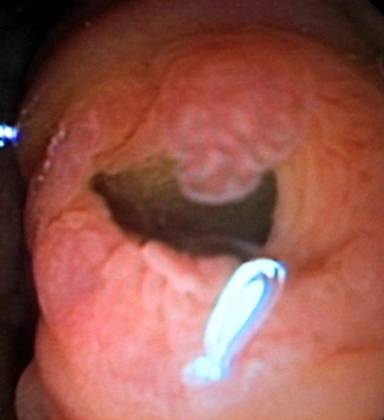

A 76-year-old female patient was admitted at hospital with diarrhea, weight loss, fatigue and abdominal pain. Her physical examination and laboratory test were normal; however, the radiological images showed an atrophic pancreas with cystic dilatation of the main pancreatic duct. Severe dilatation of the main pancreatic duct was confirmed on EUS, with the presence of round images of mucinous aggregates within (droplets of mucous plug). In view of these findings, we performed a duodenoscopy, which showed mucin extrusion from a patent ampulla (a “fish-mouth” look-like patulous papilla with mucus excretion from the orifice; Image 1), a pathognomonic finding of intraductal papillary mucinous tumor (IPMT) of the main pancreatic duct. We obtained blind biopsies and the histological results confirmed the diagnosis of IPMT. After removing the duodenoscope, a mucus string of about 40 cm in length was adhered to the biopsy channel of the duodenoscope (Image 2).

Image 1 |